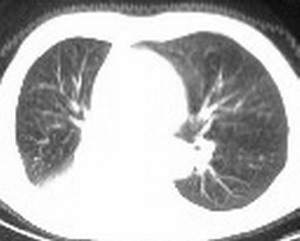

右肺下叶支气管阻塞,右下叶不张,考虑中心型肺癌伴下叶不张

先考虑:右下肺中心型肺癌伴下叶肺不张、胸腔积液

右肺下叶支气管闭塞,中间段支气管狭窄,下叶不张,胸腔及叶间积液.中心型肺癌伴下叶肺不张.胸腔和叶间积液.

考虑中心型肺癌伴下叶不张

考虑:右下肺中心型肺癌伴下叶肺不张、胸腔积液

右肺下叶支气管闭塞,伴下叶实变不张。建议增强及纤支镜。